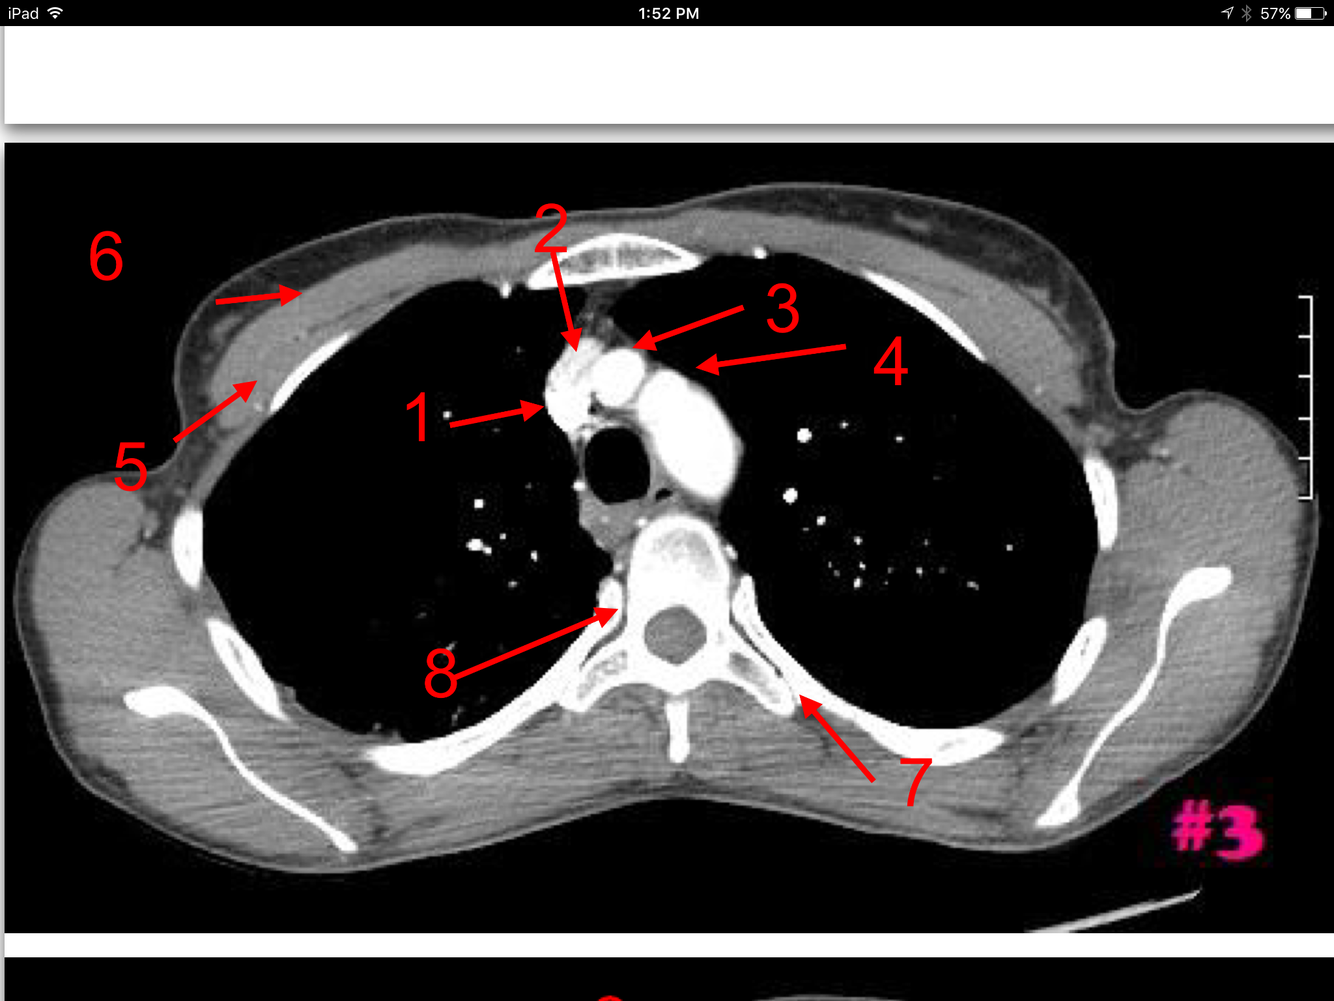

3

Rt brachiocephalic vein

Lt brachiocephalic vein

Brachiocephalic artery

Lt common carotid artery

Manubrium of the sternum

Lt subclavian artery

Esophagus